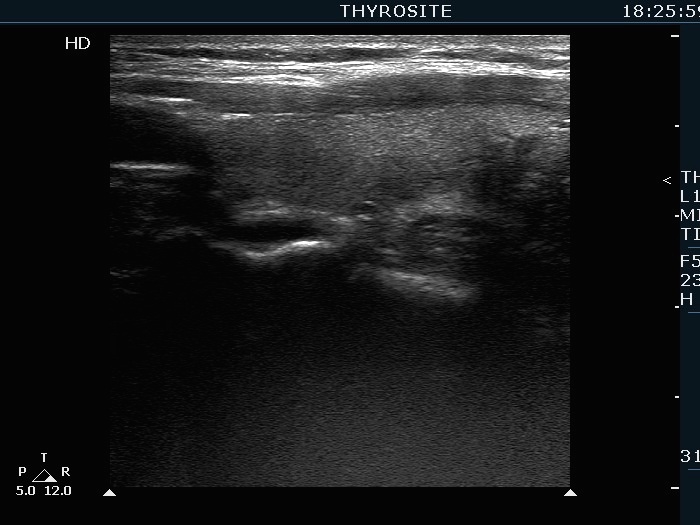

Extrathyroidal spread - case 2113 (ultrasonographic picture 11)

Left lobe, longitudinal scan.